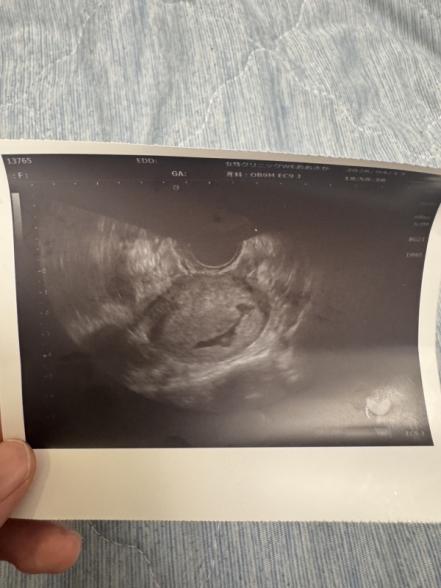

妊娠6週目 エコー写真がいびつです

初めまして。 添付させて頂きました写真のようないびつな形の胎嚢でとても不安です。 まだ心拍も確認できておらず。。。 いつも通っているクリニックさんで別で1度通院しました所、胞状奇胎の可能性があると言われ、血液検査しましたが、数値は6週目の今で2200程度でした。 6週目の今の症状はお腹の張り、頭痛、腹痛、吐き気、空嘔吐、眠気と言ったところですが、どれもめちゃくちゃしんどいって感じではないです。 出血もありませんが、大丈夫でしょうか...?

赤ちゃんの胎嚢の形についてですね。

心拍の確認はこれからということですが、同じように細長い形の胎嚢でも、順調に赤ちゃんが成長をしていくこともあります。